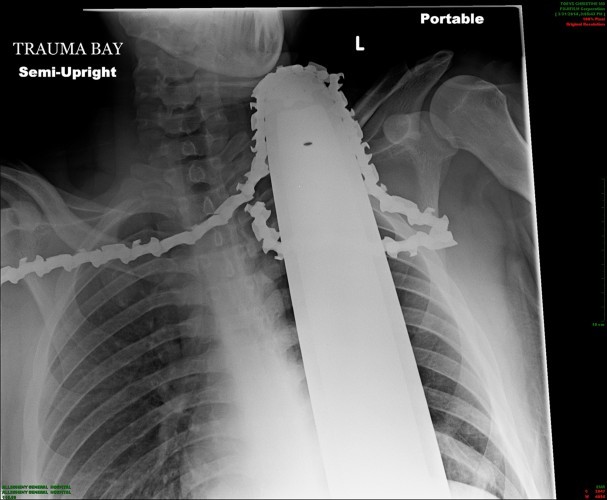

A chainsaw that cuts through trees like butter obviously can create unspeakable destruction when it kicks back and strikes its operator. Amazingly, a young tree trimmer is still around to speak about an incident that left a running chainsaw’s chain embedded in his neck. The saw’s chain snapped and it flew back and sliced about two inches into his skin, lodging the blade and chain between his collarbone and his neck. The saw was still running afterwards. The worker, James Valentine, 21, managed to shut off the chainsaw and climb down the tree he had been cutting. He survived the horrifying experience only because the saw did not strike any major arteries and instead cut into muscle tissue. Valentine successfully underwent surgery in Pittsburgh to remove the blade and chain and said he is looking forward to returning to work. Here is an X-ray showing the saw’s chain lodged in Valentine’s neck. (Photo courtesy Allegheny Health Network)